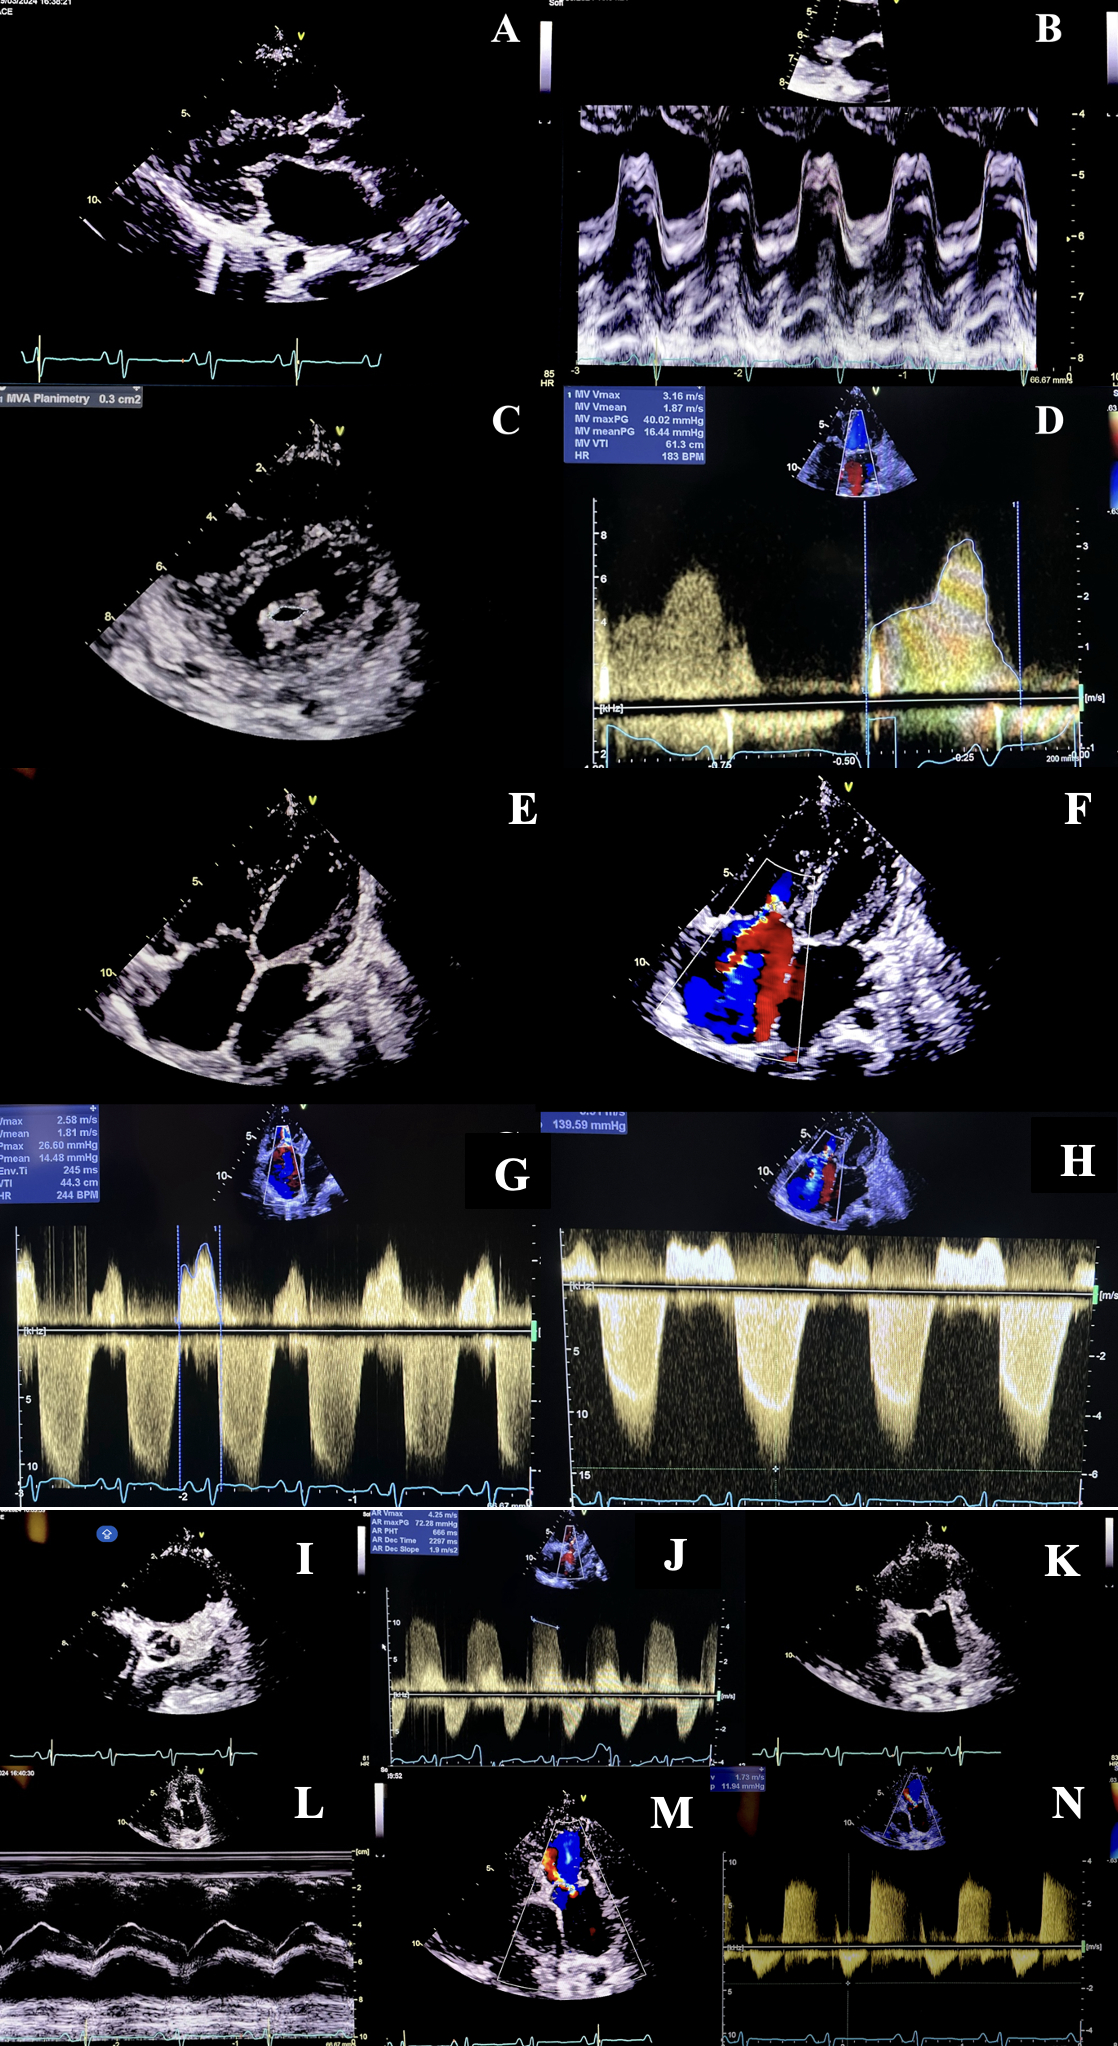

A 12-year-old boy presented with gradually progressive dyspnea over two years to current New York Heart Association (NYHA) class IV status. He was hospitalized for a week with fever, sore throat and migratory polyarthralgia three years ago. Examination- pallor, facial and pedal edema, malnutrition (height= 127 cm, weight= 27 kg, body-mass index= 16.8 kg/m2), Harrison’s sulcus, pulse= 90/minute, blood pressure= 104/64 mm of Hg, severe mitral and tricuspid stenosis, severe pulmonary arterial hypertension, and right ventricular failure. Electrocardiogram- sinus rhythm with right axis deviation and QRS morphology consistent with systemic pulmonary hypertension and severe mitral stenosis. X-Ray chest- bi-atrial enlargement with pulmonary arterial and venous hypertension. Echocardiography- severe mitral stenosis (mitral valve area= 0.3 cm2), trivial mitral regurgitation, Wilkins Score= 8/16, mean gradient= 16 mm of Hg (maximum= 40 mm of Hg), doming of the thickened tricuspid valve with severe tricuspid stenosis, thickened aortic valve leaflets with mild aortic stenosis and trivial aortic regurgitation, and doming of thickened pulmonary valve with a c notch and trivial pulmonary regurgitation. There was associated severe pulmonary hypertension (suprasystemic) with right ventricular systolic pressure of 140 mm of Hg.

In view of young age, malnutrition and a fulminant presentation of severe mitral and tricuspid stenosis, the management hinged around the percutaneous versus the surgical options. Key factors included young age, financial constraints, and repeated reluctance of parents for open heart surgery. The patient underwent a percutaneous dilation of mitral and tricuspid stenosis with an Inoue balloon in a single intervention.